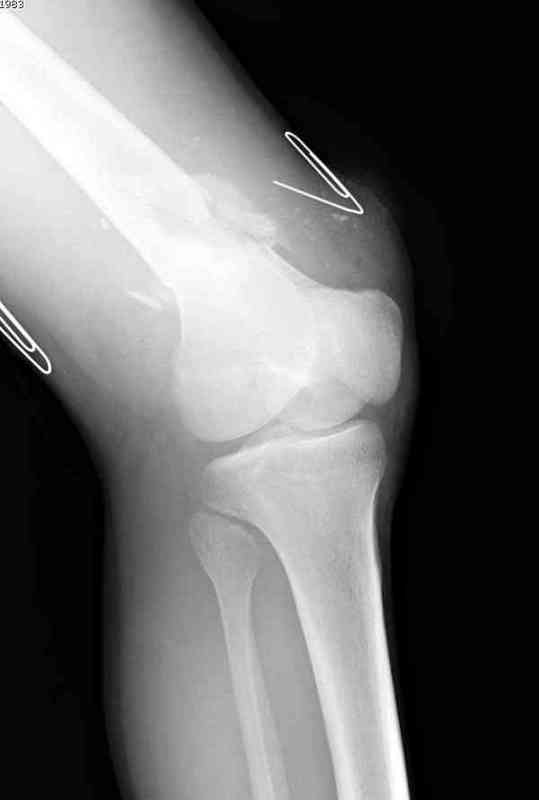

Укороченный фрагмент с самого начала являлся проблемным, на рентгене не видны следы от множественных спиц, обычно применяемых для лечения "коротких" переломов.

Адекватную фиксацию можно получить путем экстрафокальной косой остеотомии более проксимально, тем самым удлинить дистальный фрагмент, без повторной работы в фокусе патологии, что, в свою очередь, приведет к еще большему укорочению фрагмента.

Как предлагают коллеги, свежие стрессовые снимки уточнят наличие подвижности, а длинный на всю длину конечности снимок позволит провести точный предоперационный расчет по коррекции.

Предпочтительно фиксацию провести пластинами, во-первых, можно было сделать квадрицепс-пластику по Judet для восстановления движения в суставе, а потом коррекцию и фиксацию кондилярной пластиной с угловой стабильностью. Стерильный турникет на конечность поможет уменьшить кровепотерю во время операции.

До выхода Locking Plate, 95 градусная Blade Plate считалась одним из первых locking concept и фаворитов в лечении супракондилярных переломов и осложнений, потому что лезвие внедряясь параллельно к суставу, что создавало хорошую фиксацию. Для усиления фиксации иногда применяли Schuhli nut, чтобы блокировать шуруп в отверстии

(первый прототип locking concept)